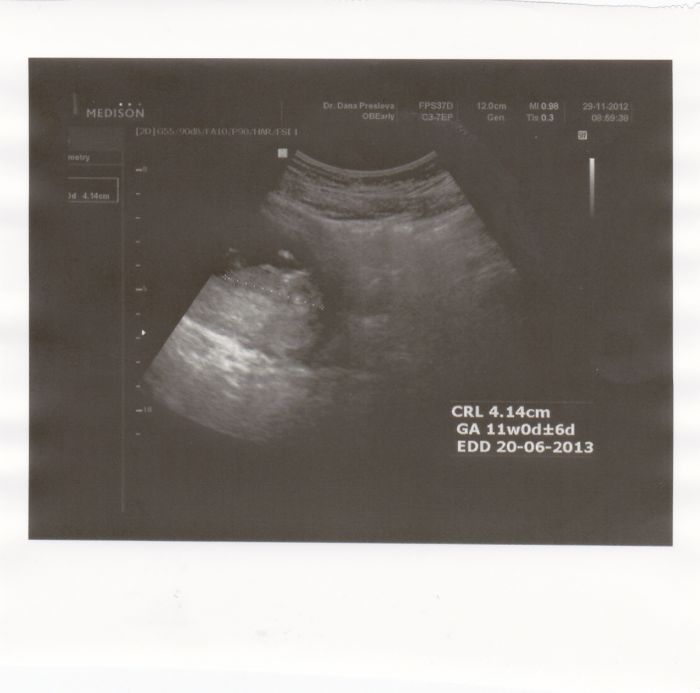

teda to mimi mi prijde jen takova cmouha... :( my mame ve 12tt a vypada jak male mimco akorat jen 6,7cm velke :) ja platim jen 50,- za foto :) zde ho pridavam jak mimisek minuly tyden vypadal :)